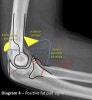

Anterior fat pad sign : 70-80% Intra-articular fracture

Posterior fat pad sign : 90% Intra-articular fracture.

- Sail sign

The anterior fat pad can be displaced up and out by fluid in the elbow joint, creating the "sail sign". This usually indicates a fracture in children in the setting of an injury.

Fluid in the elbow joint can displace the fat pad up and out making it visible on the lateral view.

Indicates that the patient has sustained an intra-articular injury. Importantly, it does not indicate that the patient has definitely sustained an intra-articular bony injury.